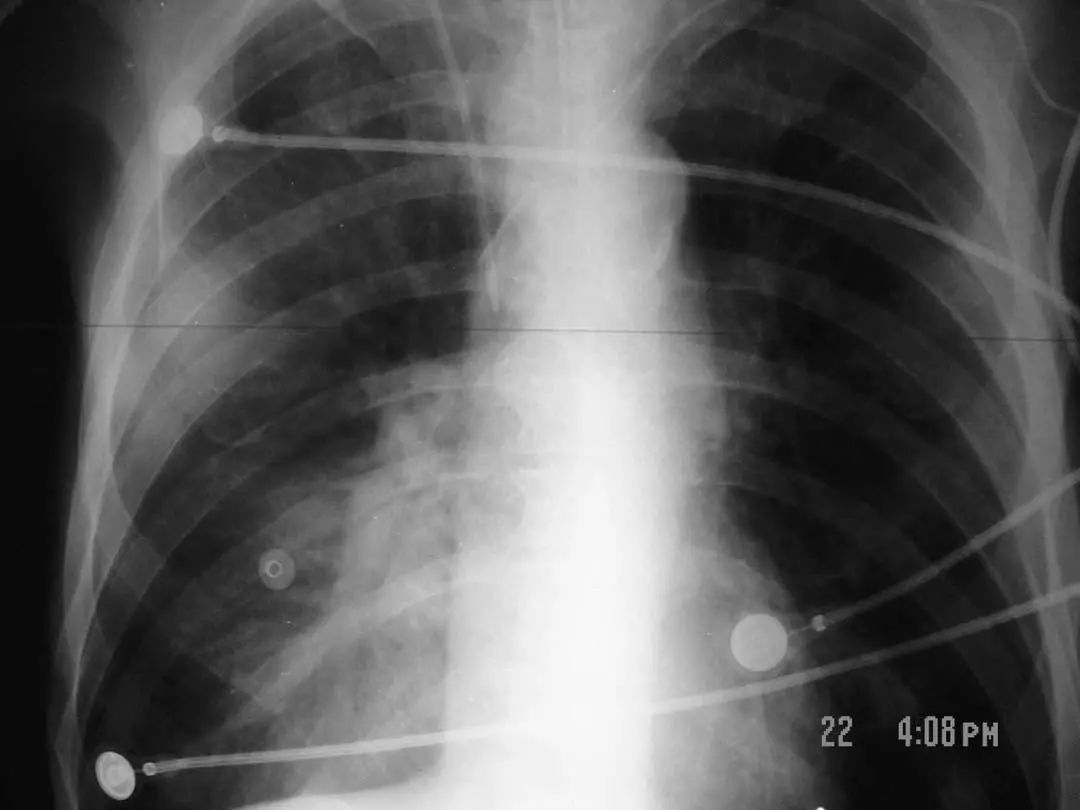

图1.1 细菌性肺炎。右上叶肺炎患者的放射影像。胸廓前后径增大,提示有慢性阻塞性肺疾病(COPD)。